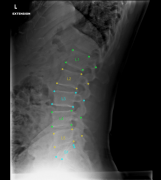

SpindleX is a revolutionary AI reporting assistant for spinal stress X-Rays. It generates fully automated reports that quantify all abnormalities and features of injuries or early degeneration.